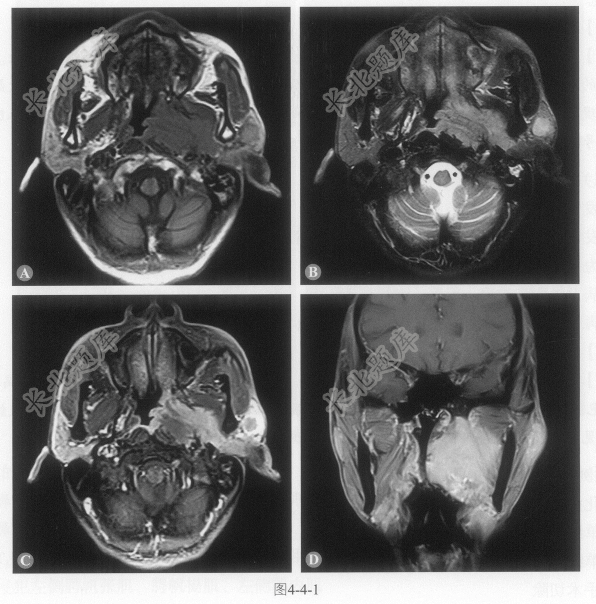

- [材料题] 患者男性,64岁,发现颈部肿物20余天,夜间疼痛,左耳听力下降,伴有鼻塞,查体:肿物质硬、可活动。MRI图像如图4-4-1。

A、鼻咽左侧壁、顶后壁明显增厚形成不规则软组织样信号肿物

B、鼻咽肿物呈T

等信号、T2稍高信号,增强扫描明显强化C、侵犯左侧腭帆张肌、腭帆提肌、左侧翼内外肌

D、侵犯左侧咽旁间隙、左侧椎前肌、左侧鼻后孔

E、左侧腮腺内可见一T

等信号、T2稍高信号结节